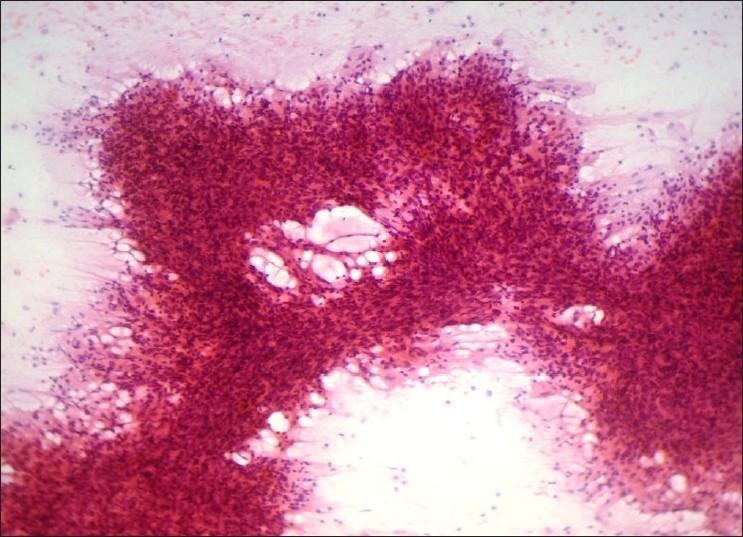

Present study was undertaken to evaluate the feasibility of application of systematic pattern analysis based on morphology in diagnosing breast aspirates.

This is a retrospective study of FNAC of the breast done over a period of 4 years in a tertiary care centre. A total of 225 cases of breast lesions for which FNAC was done with histological follow-up were included in the study. Breast aspirates were provisionally diagnosed based on systematic pattern analysis. Aspirates were grouped into six categories based on predominant cellular pattern, and correlation between cytological and histological diagnosis was assessed.

Application of pattern analysis on FNAC of breast lesions in our study had a sensitivity of 94.5%, specificity of 98%, diagnostic accuracy of 97%, positive predictive value of 95.8%, and negative predictive value of 97.4%.

Systematic pattern analysis based on morphology of FNAC smears was found to be highly reliable and could be easily reproducible in the assessment of breast masses.